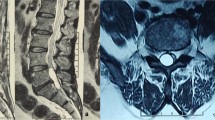

A 48-yr old autorikshaw driver presented with weakness of fingers and lower limbs. All sensations were decreased below xiphisternum(T6). The gait was spastic. Magnetic Resonance Imaging(MRI) showed an extramedullary intradural cyst at C7-T1 level. It was hypointense on T1-weighted image and hyperintense on T2-weighted image. There was no enhancement with contrast. C7/T1 Laminectomy was done. On gentle retraction of the cord, a whitish cyst was seen. Some clear fluid was aspirated and cyst was excised en toto. Myelopathy improved over two weeks. Histopathological examination showed a cyst wall composed of fibrocollagenous tissue, and lined by pseudostratified epithelium containing many goblet cells and having focal ciliation. The findings were consistent with neurenteric cyst. Follow-up MRI after five years showed no recurrence.